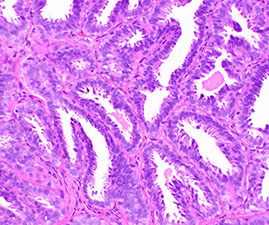

Traditional Serrated Adenoma (TSA)

- aka serrated adenoma

Left or distal colon, pedunculated

Majority are rectosigmoid

- similar ca risk as adenomas

Micro: complex villous architecture c crypts that lose orientation to muscularis mucosa (aka ectopic crypt formation [ECF])

Hyperplastic architecture + adenoma changes

(+) KRAS mutations and CpG island methylation and are beleived to be cancer precursors; although they lack MSI